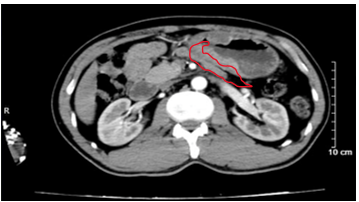

- CTscanner bụng: Dày thành hang vị dạ dày, dày không đều, mất cấu trúc lớp bề dày khoảng 18mm, trên đoạn dày khoảng 75mm, sau tiêm ngấm thuốc, không thấy thâm nhiễm, cạnh bờ cong lớn và bờ cong nhỏ lân cận có vài hạch (>5 hạch), hạch lớn nhất kích thước 16 x 10mm, sau tiêm ngấm thuốc.

Hình 2. Hình ảnh chụp cắt lớp vi tính ổ bụng. Hình ảnh dày thành hang vị dạ dày, mất cấu trúc lớp, bề dày khoảng 18mm, sau tiêm ngấm thuốc (vòng tròn màu đỏ)